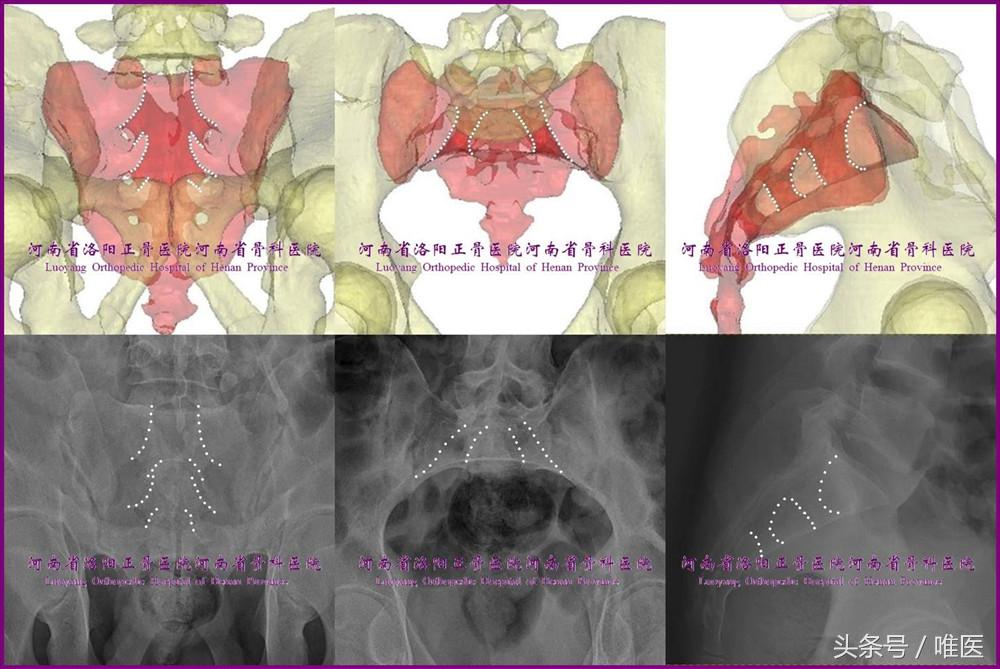

二、骶髂螺钉的适应证

理论上,只要SJI耳状面及其后部所对应的髂骨外板(进钉点区域)的骨质结构完整,那么其就可用于治疗:

①SIJ脱位;

②各种类型(经髂骨、经骶骨或经两者的)的SIJ骨折脱位;

③多种类型【Denis zone1-3,包括U/H/Y等形自杀跳楼骨折(suicidal jumper’s fracture)及脊柱骨盆分离(spinal pelvic dissociation)】的骶骨骨折。(图2)

图2. 骶髂螺钉的适应症。从左至右依次为SIJ脱位、SIJ骨折脱位、H形骶骨骨折。